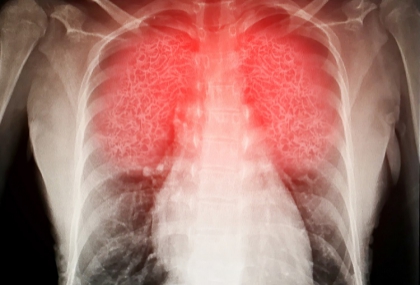

根據世界衞生組織(WHO)和國際癌症研究機構(IARC)的數據,肺癌是全球癌症死亡的主要原因。2020年,肺癌導致約180萬人死亡,占癌症總死亡數的18%。

肺癌初期的症狀通常並不明顯,若出現胸悶、胸痛、超過兩周的持續咳嗽、咳嗽帶血絲、聲音沙啞、食慾不振,可能是肺部異常警訊,都該多加留意並及早就醫檢查。